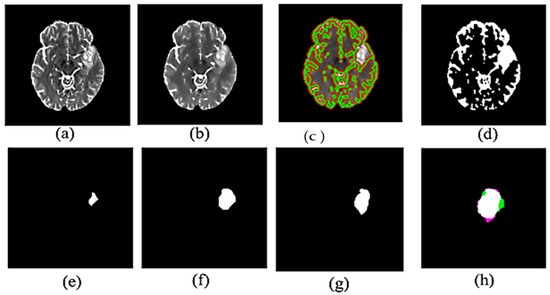

3.1. Proposed Method Results